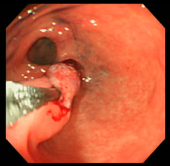

| 症例(胃ポリープ切除1) | |||

| ポリープ | 根元に生理食塩水を注入して水ぶくれ状態をつくり、膨らんだその部分に スネアをかけて高周波の電流を流し病変部を焼き切っている状態。 |